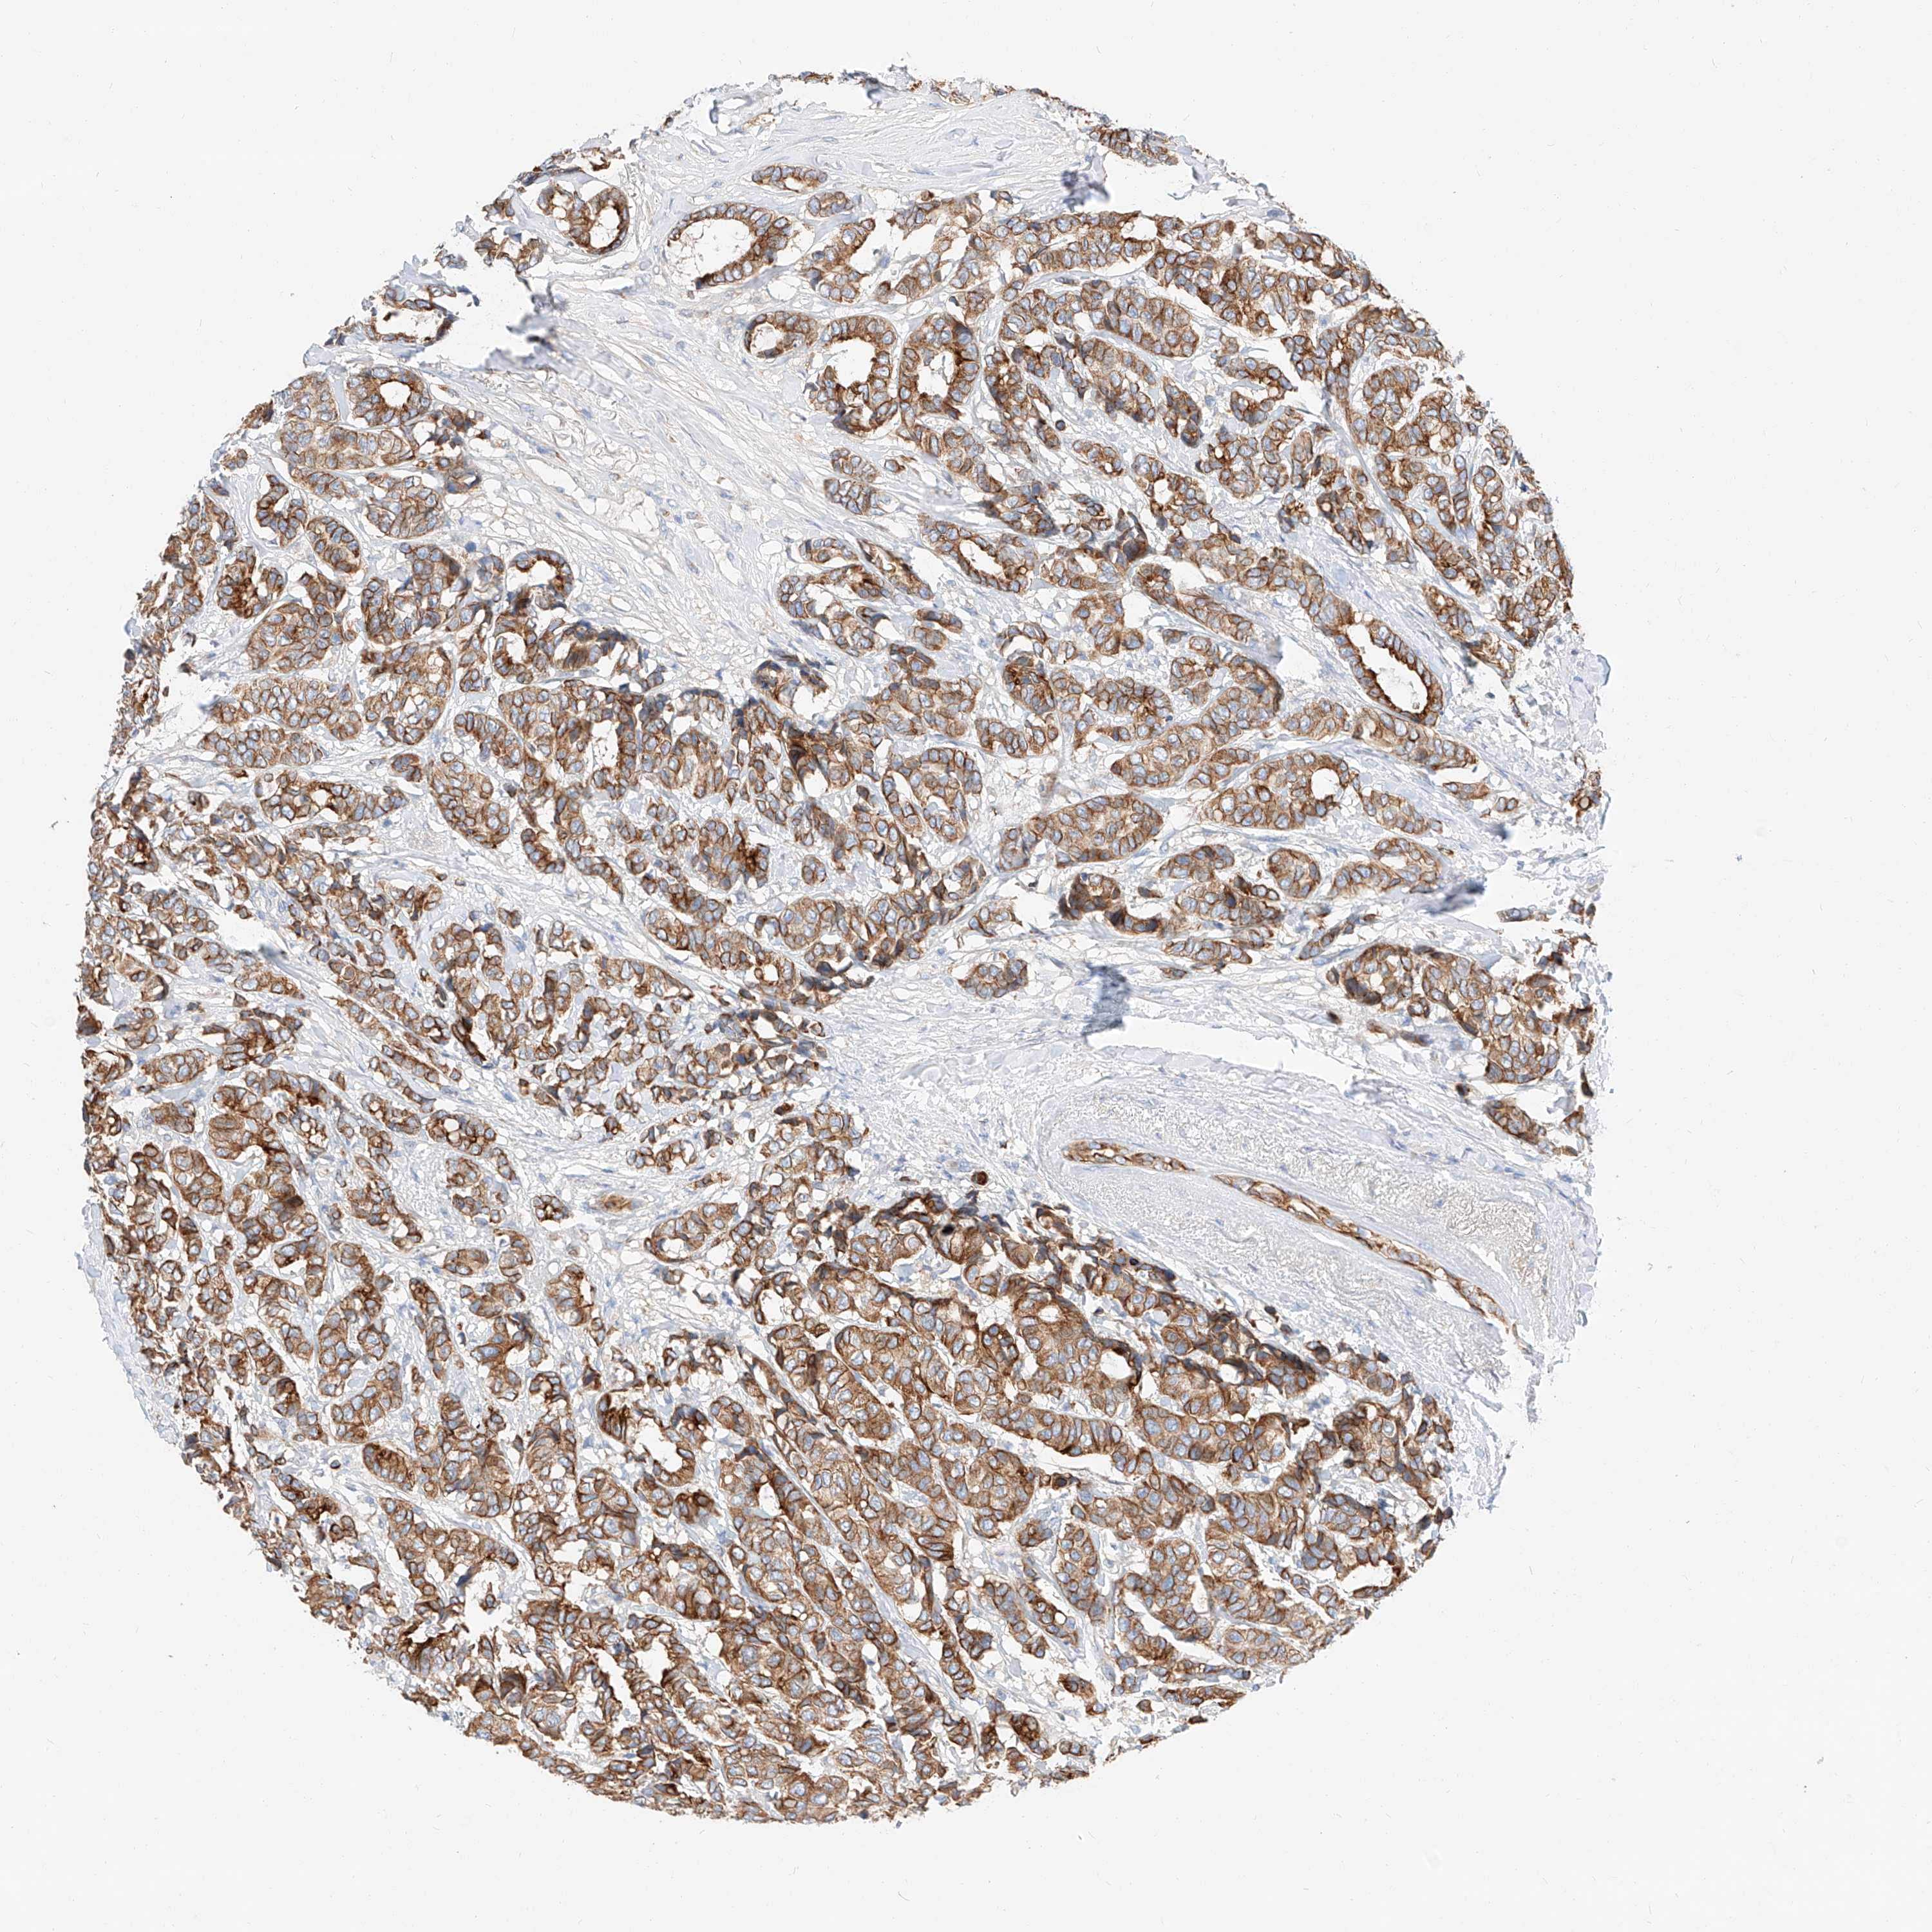

CANCER BREAST CANCER Show tissue menu

BRCA TCGA BRCA VALIDATION PROTEIN EXPRESSION